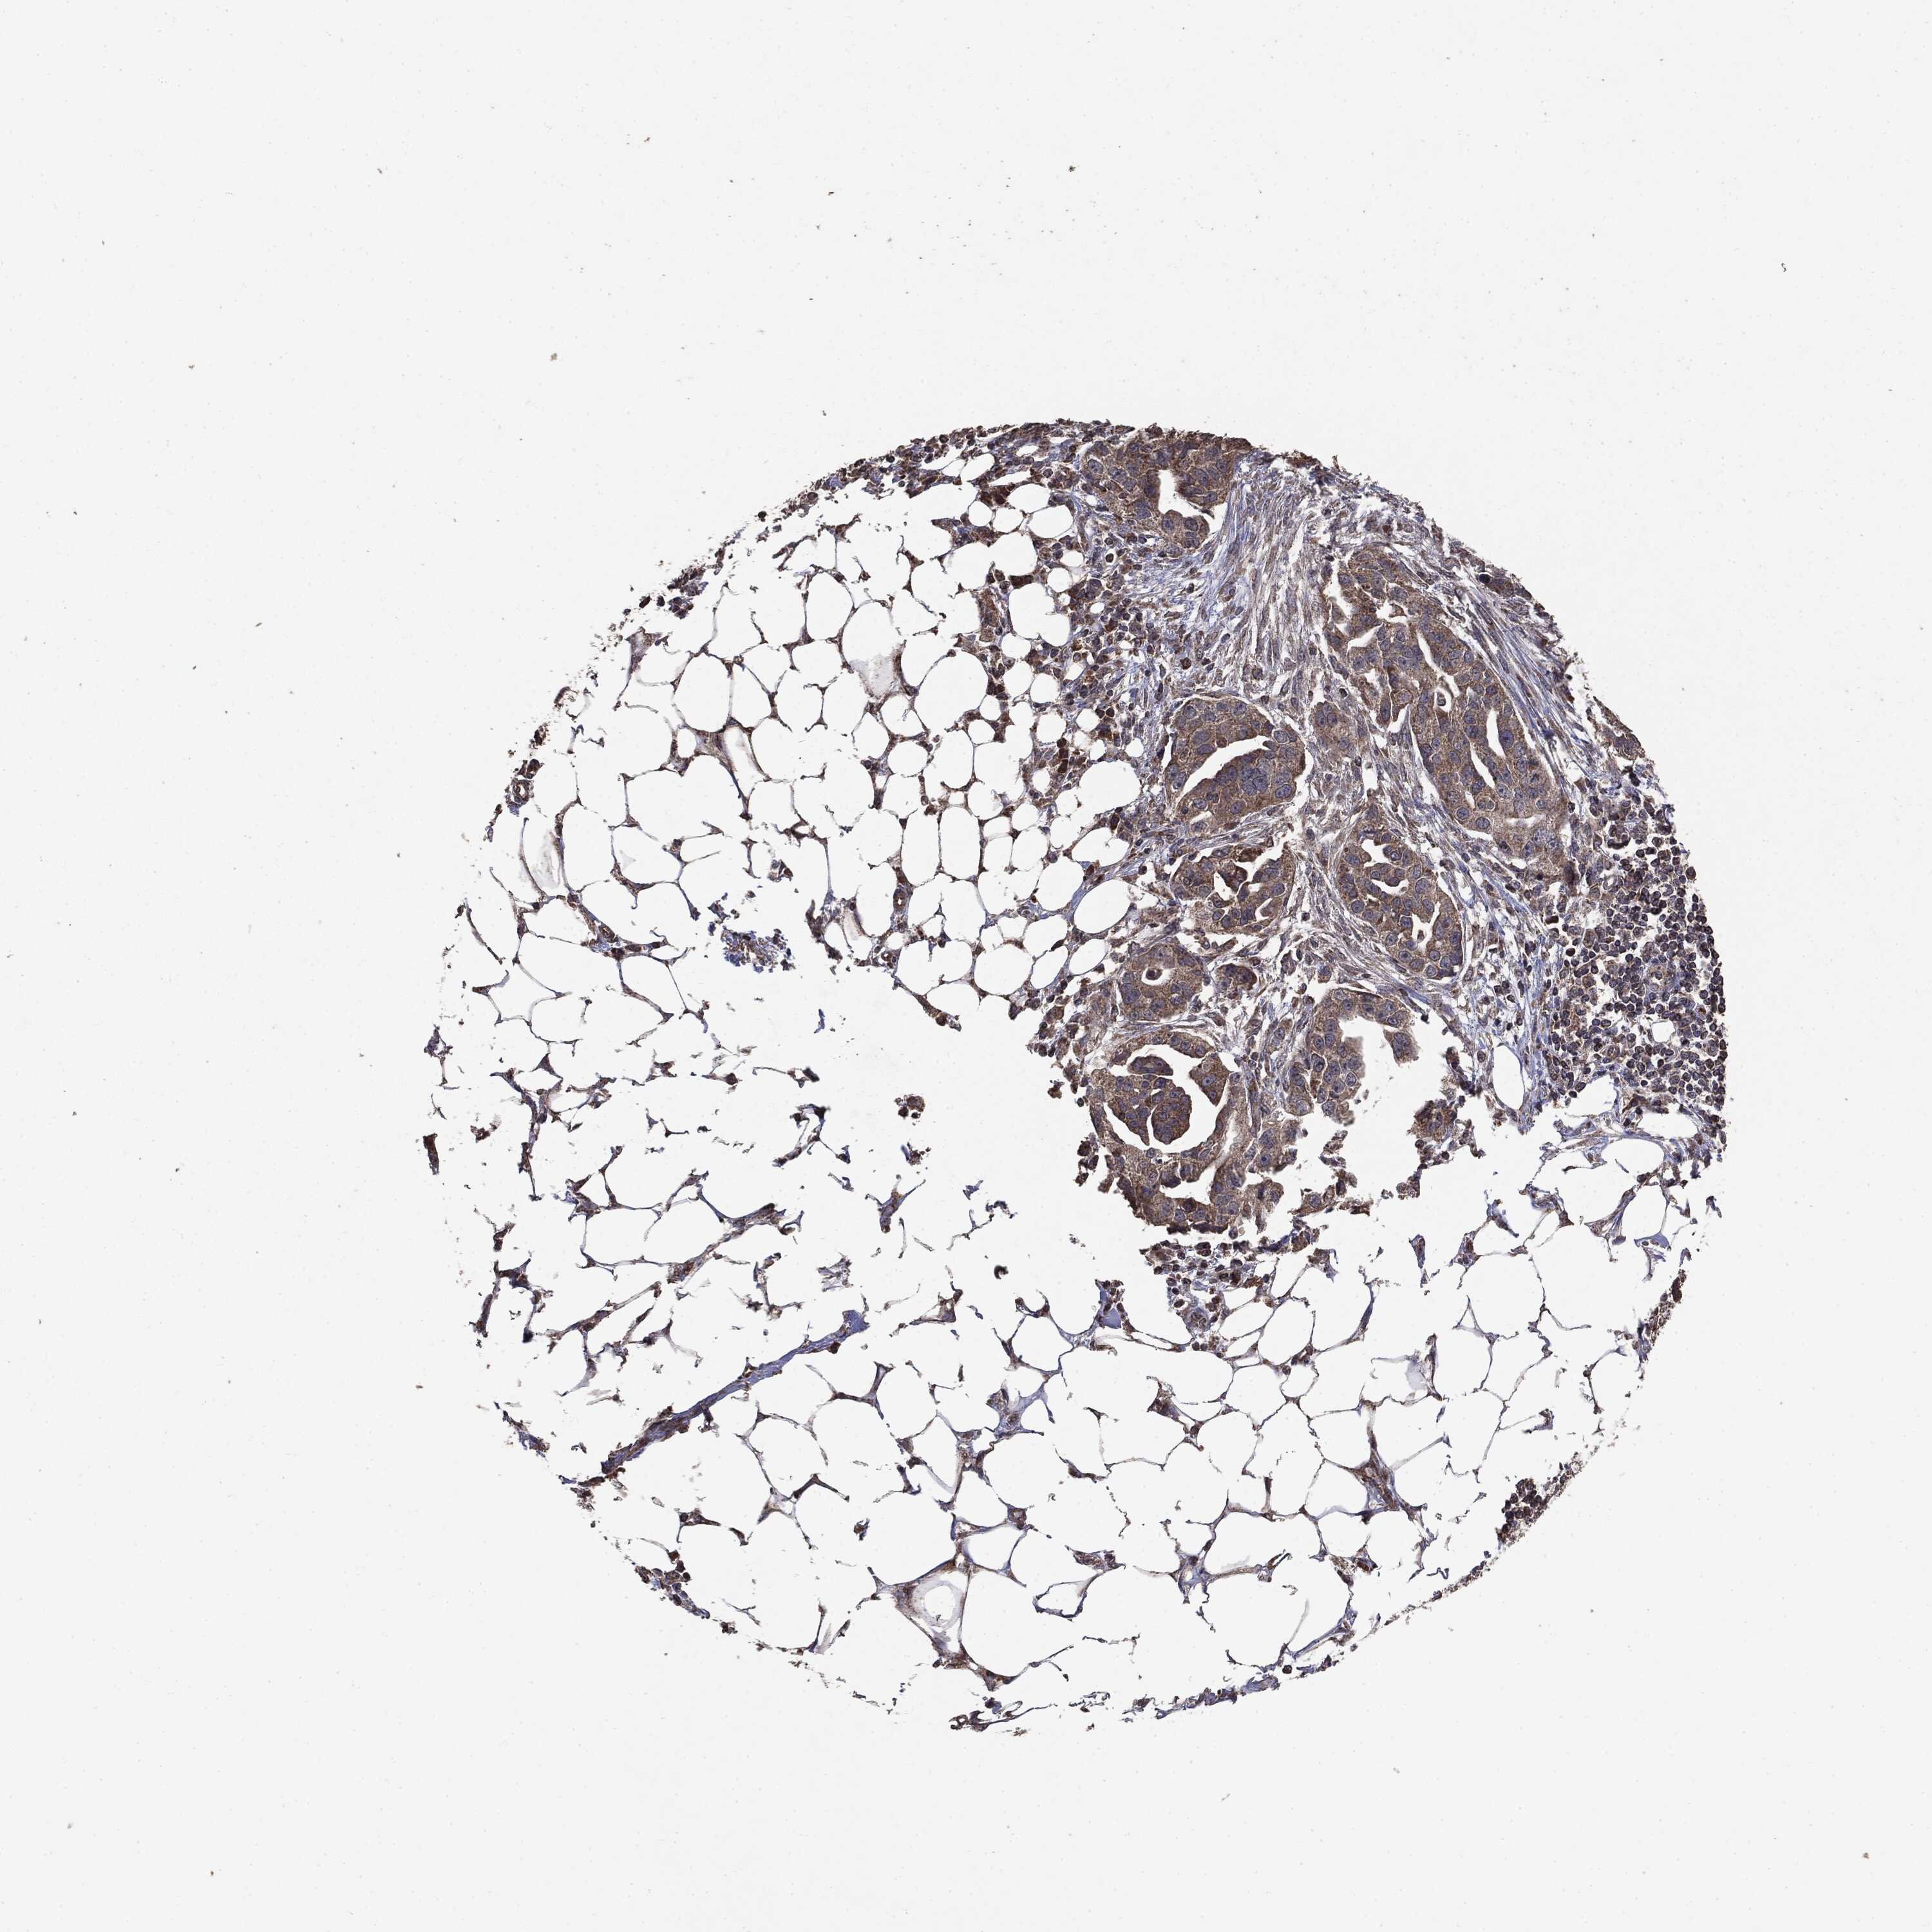

OVARIAN CANCER - Protein expressioni

A mouse-over function shows sample information and annotation data. Click on an image to view it in a full screen mode. Samples can be filtered based on level of antibody staining by selecting one or several of the following categories: high, medium, low and not detected. The assay and annotation is described here.

Note that samples used for immunohistochemistry by the Human Protein Atlas do not correspond to samples in the TCGA dataset.

Antibody stainingi

Antibody staining in the annotated cell types in the current human tissue is reported as not detected, low, medium, or high, based on conventional immunohistochemistry profiling in selected tissues. This score is based on the combination of the staining intensity and fraction of stained cells.

Each image is clickable and will lead to virtual microscopy that enables deeper exploration of all samples and also displays staining intensity scores, fraction scores and subcellular localization as well as patient and tissue information for each sample.

CAB080065

Cystadenocarcinoma, mucinous, NOS